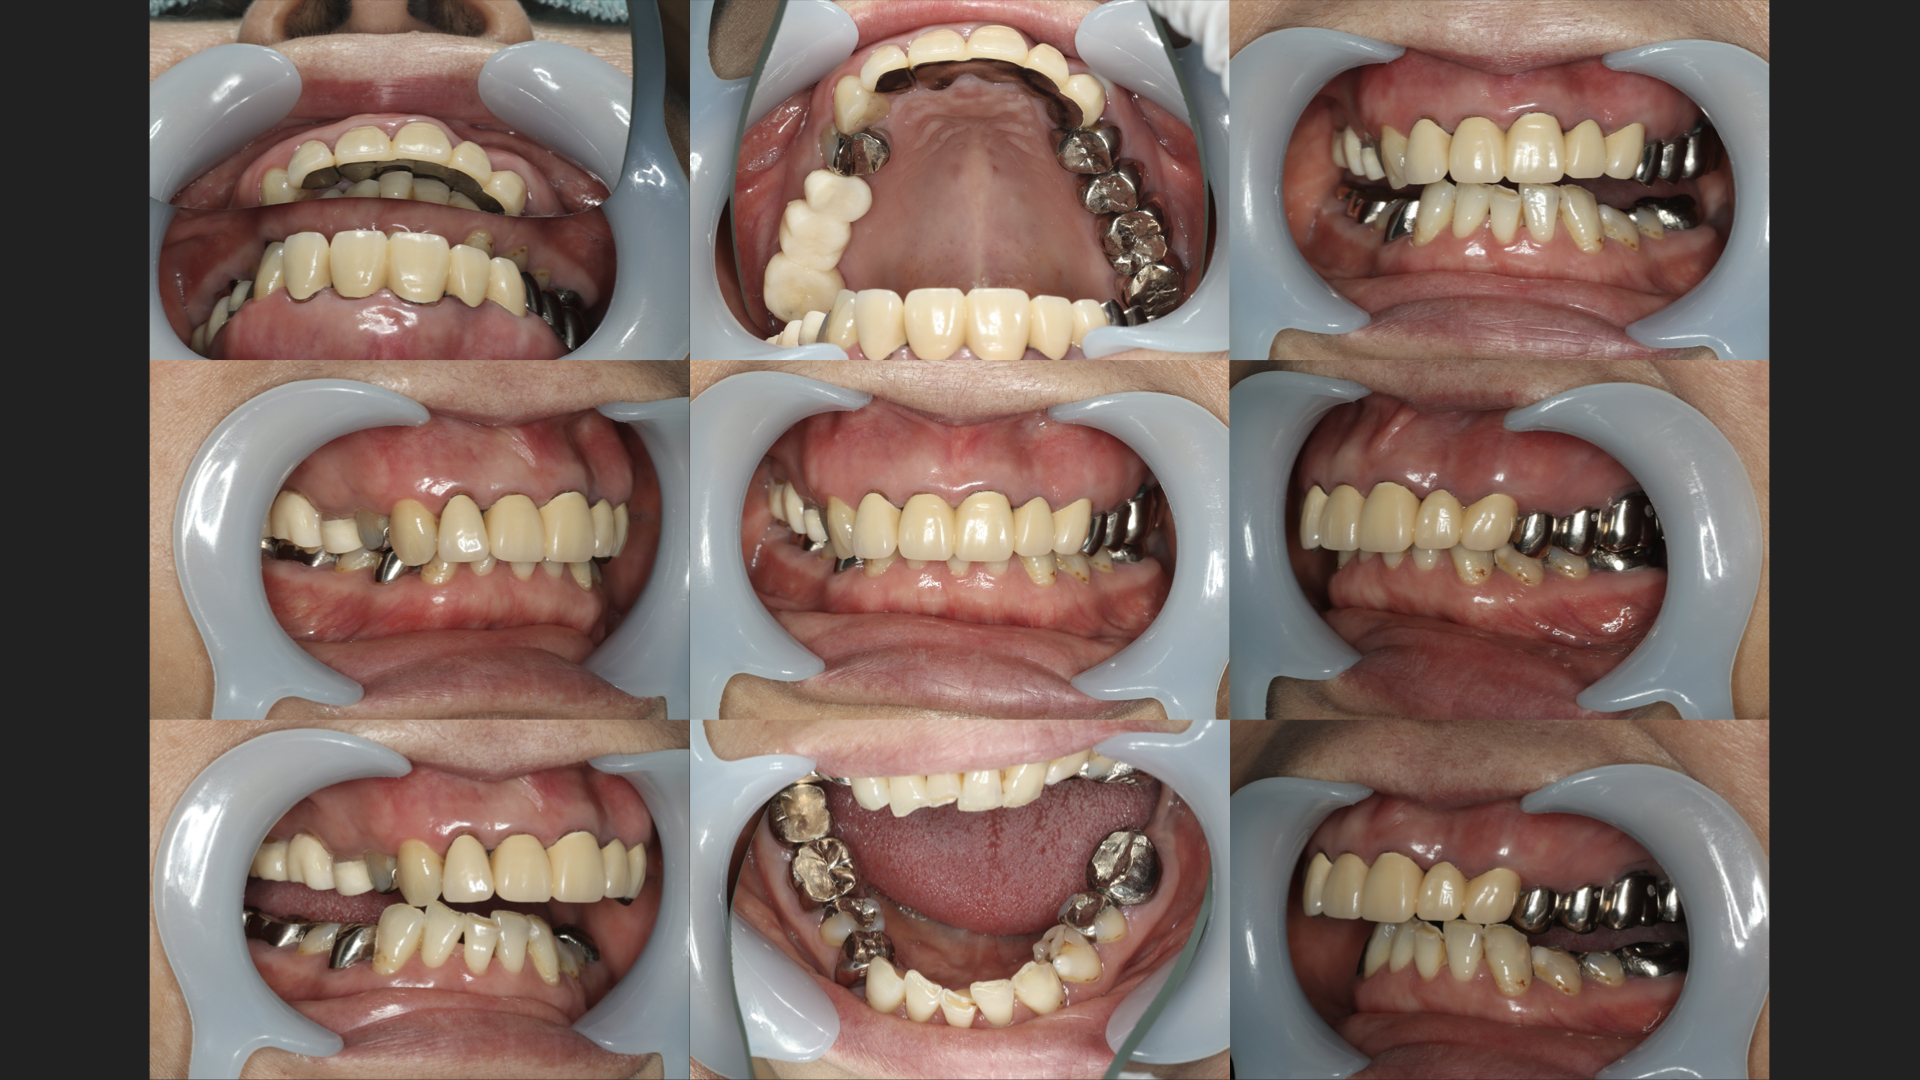

勉強会で発表した咬合再構成の症例です。

1歯1歯の治療のクオリティはもちろんのこと、全体を捉え、最初から最後まで辻褄が合うように最初からかなりしっかり計画しないといけません。

この症例には、

セラミック

インプラント

矯正

の全てが関わっています。

計画に間違いがあったら当然最後はうまくいきません。

計画が間違っていないか判断する、全体を捉える能力が必要です。

また、その計画通りに実行できる能力が必要です。

1歯での誤差が、何本も誤差が起こると全体的な不整合がどんどん大きくなります。

治療前の歯の状態を見ただけで、治療後の最修形が見えるかどうか・未来が見えるかどうかが歯科医師の実力なのではないか、と最近は考えています。

「とりあえず悪いから削ろっか!!」ではダメだと今は思います、「こういう最後になるからこういう風に治療しないといけない」と思えるように、日々勉強して患者さんの治療に向き合っています。